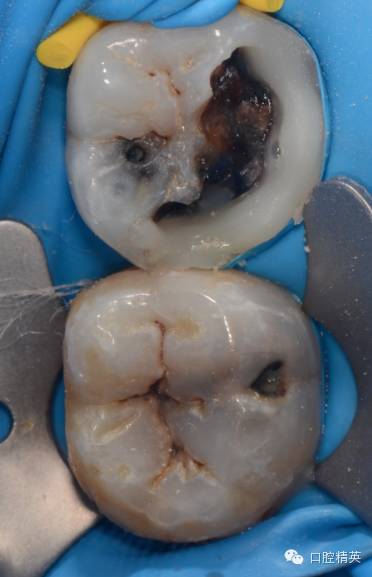

然后开始去腐,我习惯用金刚砂球钻先从边缘去腐,最后开髓,最好不要用裂钻直接开髓,第一可以避免底穿,第二避免腐质飞沫污染髓腔,给rct带来麻烦。

开髓,揭净髓顶,直线通道车针逐步建立直线通路,大量次氯酸钠冲洗,探查根管长度,次氯酸钠和edta交替冲洗根管

tf镍钛锉预备至30#06锥度(虽然根尖区域的预备应该在35#~40#)但我认为这不是根尖周炎,所以仅仅预备到30#,大量次氯酸钠荡洗根管,根充还是用的iroot糊剂和热牙胶,我用的是思博安的热牙胶,很多同行和我说,相比韩国的产品思博安的成本太高了,但思博安的牙胶是 β象限的,低温时的流动性更好,更容易进入狭窄部位和侧支根管,所以我认为,相对与更好的治疗效果,成本并不重要。

近中根管的侧枝清晰可见